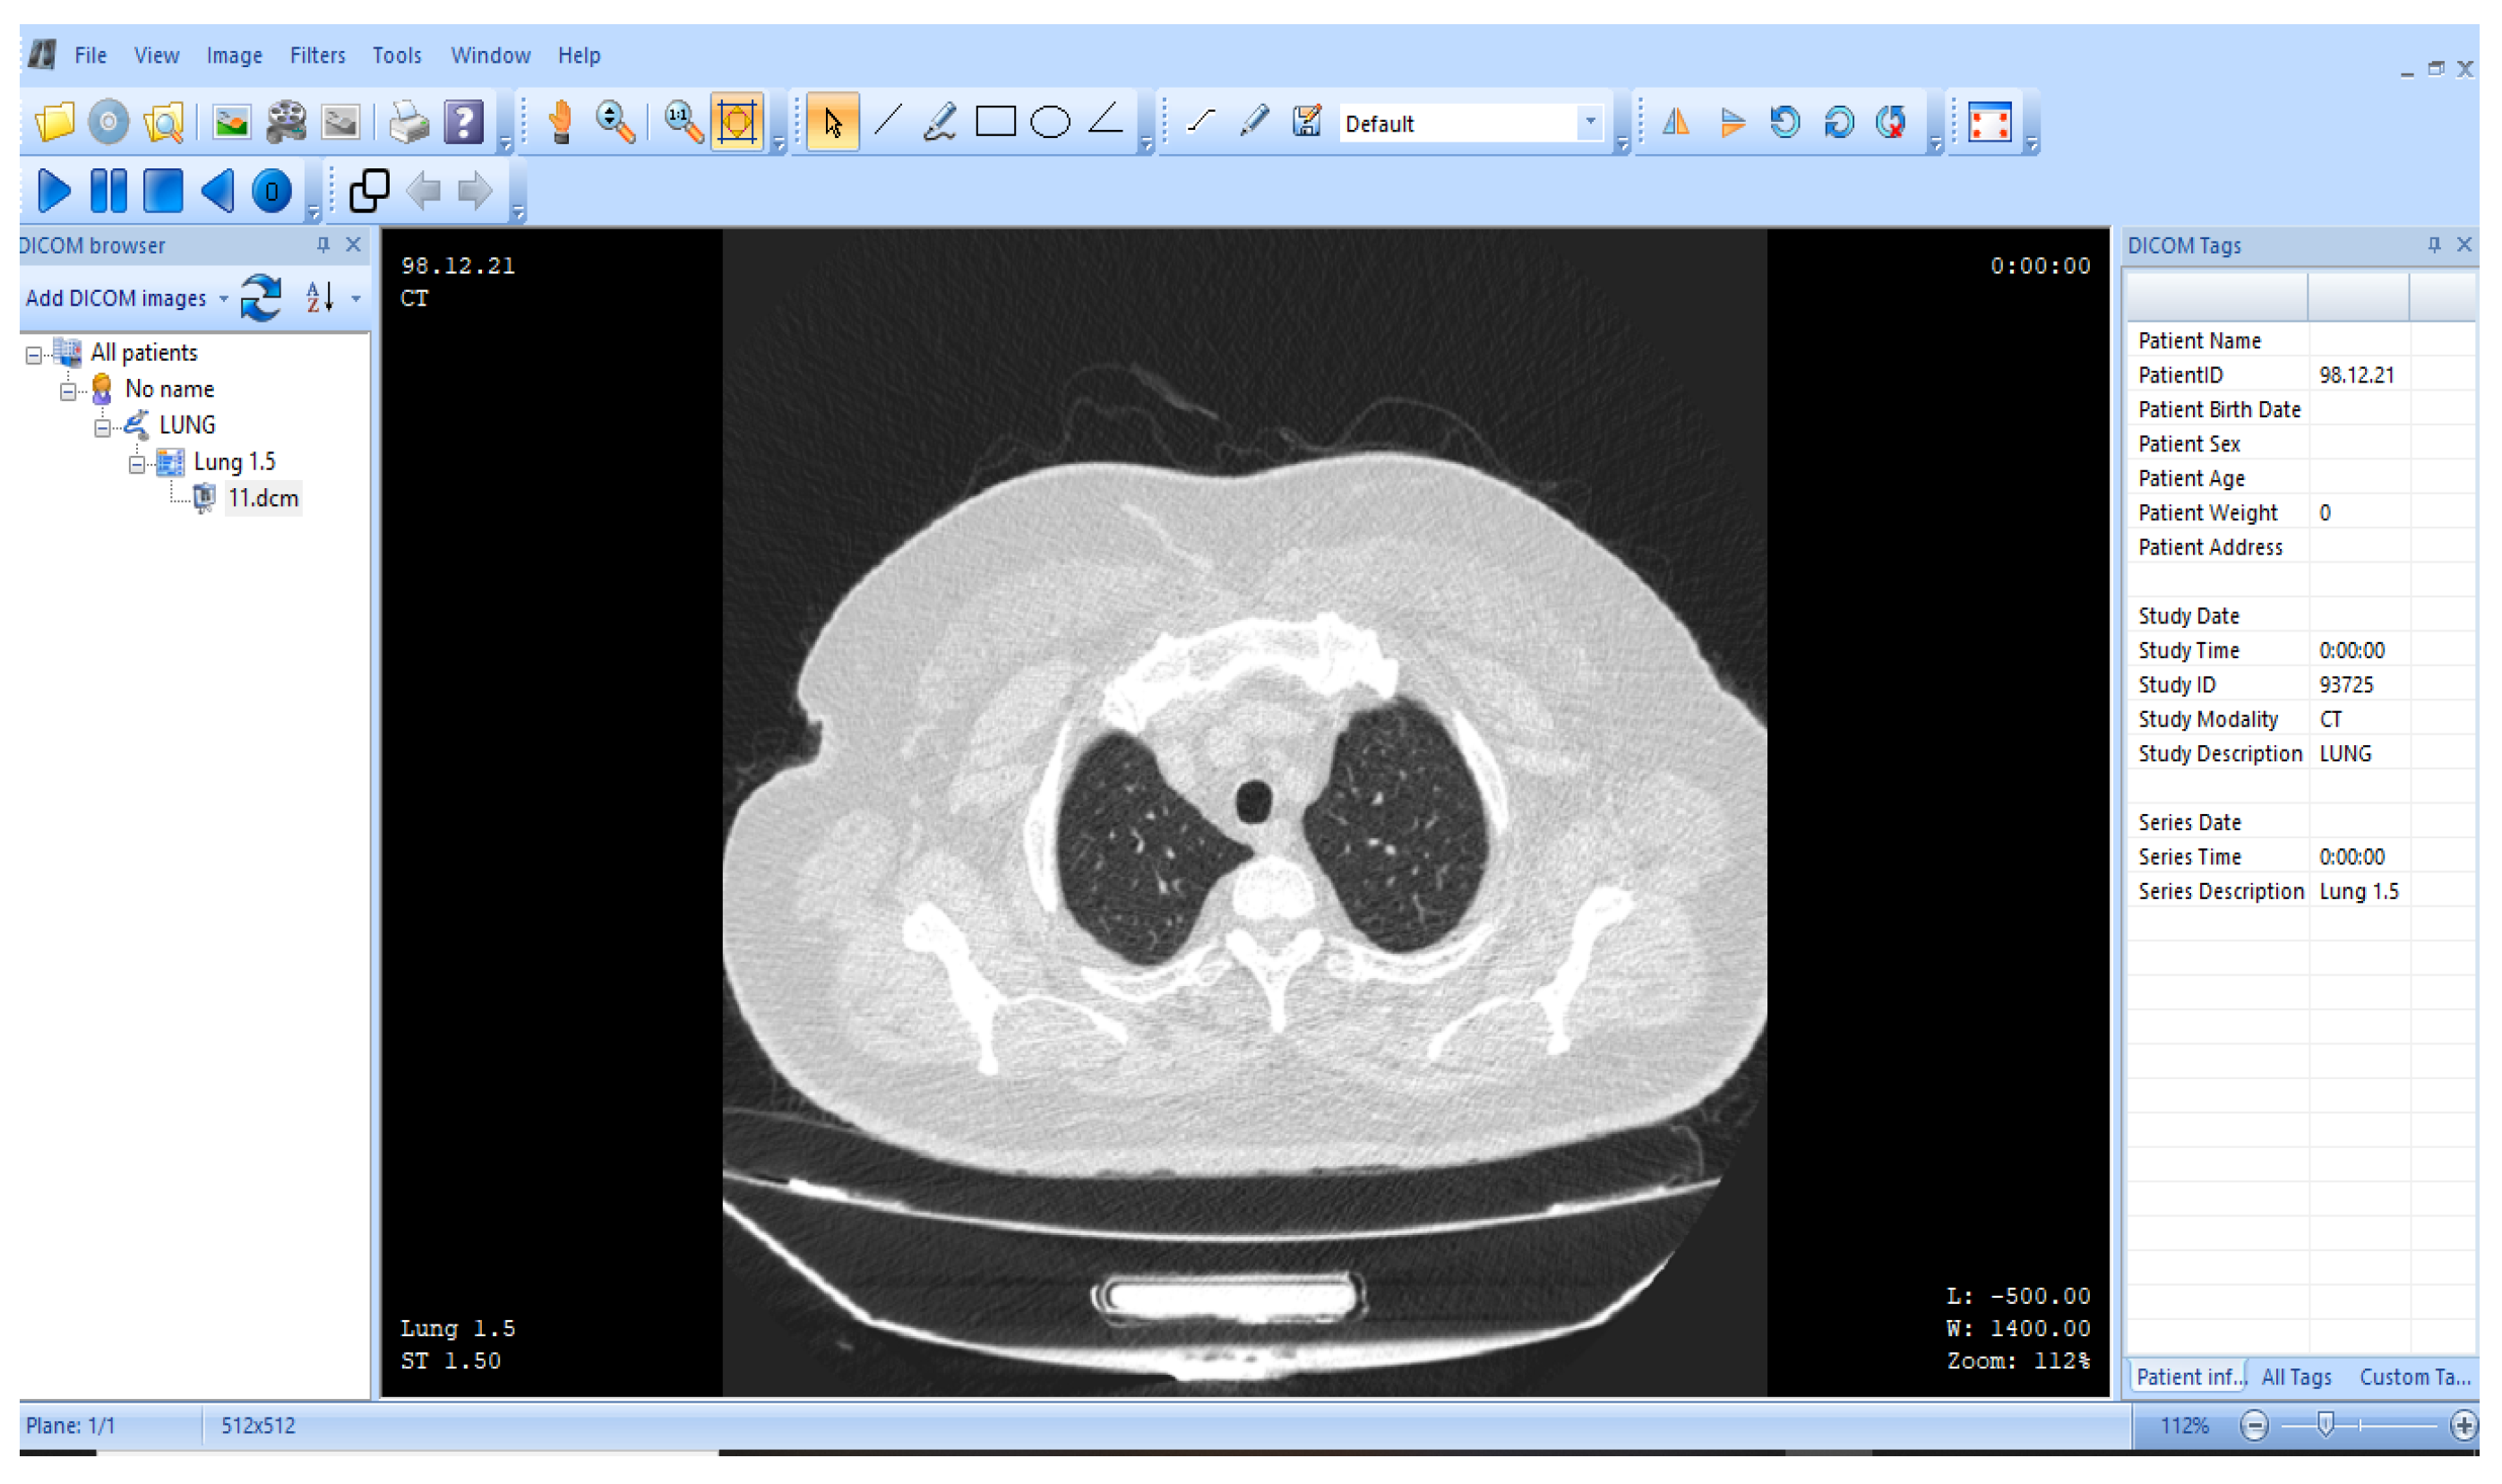

Figure 10 presents the view of the DICOM image under observation. MicroDICOM software (DICOM Viewer 2023) is used to analyze the DICOM image of the human body. The DICOM image has dimensions of . The “computed tomography (CT)” scan image used in this work shows a human lung. Since the proposed methodology is developed to be implemented on medical images, DICOM images are best suited for this application. The image compression of the DICOM is performed with the assistance of Matlab 2018 (b), with an operating system having a processor, and a hard drive.

Figure 10.

representation of the human lung (MicroDICOM) [85].